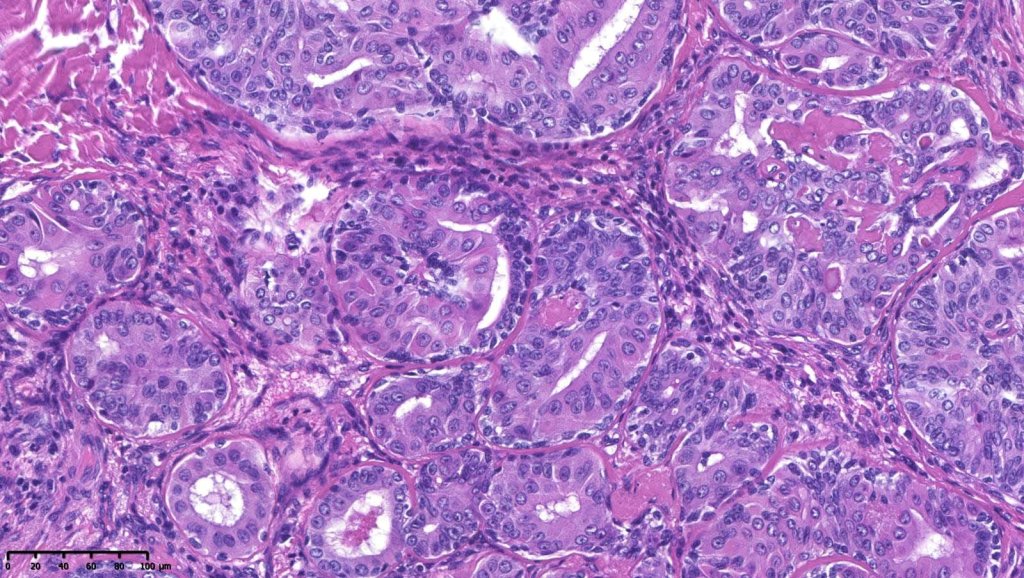

Histological features

•Solid or cystic sharply defined nodule in dermis sometimes extending into subcutaneous fat

•Generally composed of an admixture of small eosinophilic cells & glycogen-rich larger clear cells

•Round to oval vesicular nuclei with small nucleoli or hyperchromatic nuclei

•Ductal and glandular differentiation

•Goblet cells are not uncommon

•Hyaline collagenous stroma